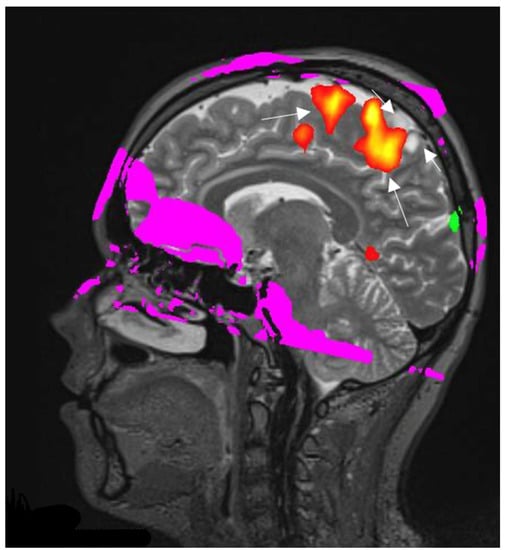

3.4.2. fMRI